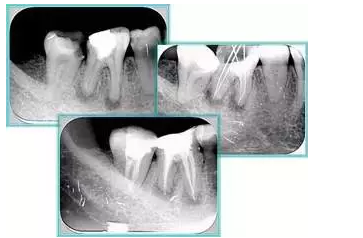

7. 器械折斷

右圖及下圖為器械折斷的 X 線片。箭頭處示折斷器械。

解決方法: ( 1 )取出。 ( 2 )通過。 ( 3 )重新確定工作長度,充填。 ( 4 )根尖手術(shù)。

器械折斷可以不用取出,取出的原因多是患者心理因素。留在里面的器械關(guān)鍵是進(jìn)行消毒,預(yù)防性使用抗感染藥物,預(yù)防感染。

二、臺階

定義:根管內(nèi)壁上人為產(chǎn)生的不規(guī)則形狀阻止器械順利進(jìn)入根尖。

原因:器械沒有預(yù)彎,根向壓力過大。

右圖箭頭處示臺階形成。